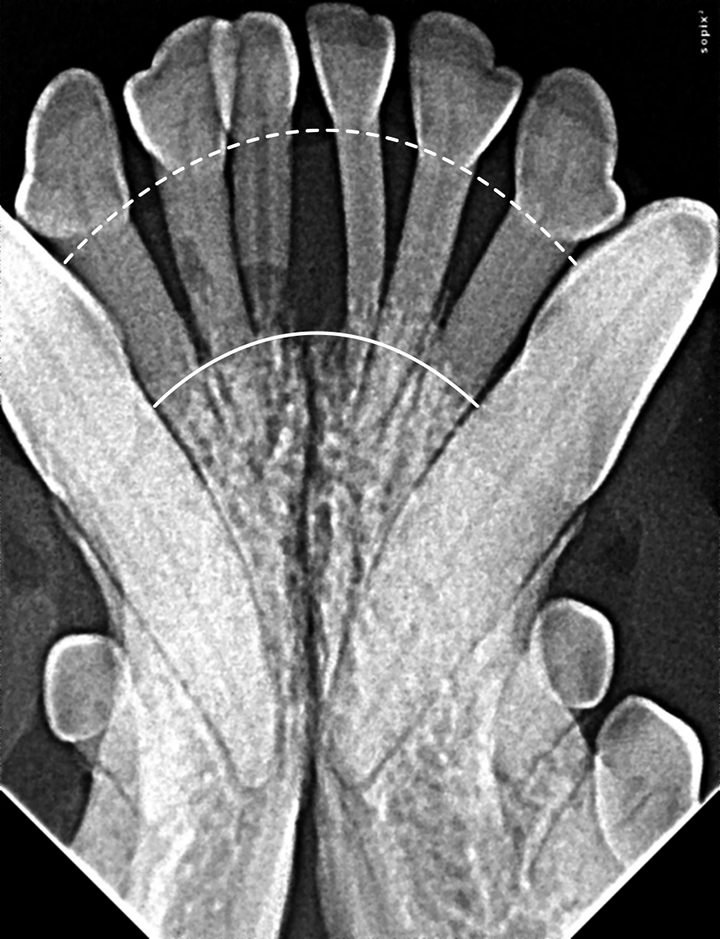

Dental Radiography Taking the Xrays OSU CVM Veterinary Clinical Dental Radiographs Practice the american dental association (ada) has various policies and recommendations to help dentists ensure that patients’. the european academy of paediatric dentistry (eapd) proposes this best clinical practice guidance to help. quiz yourself with questions and answers for dental radiology practice test, so you can be ready for test day. This article provides the fundamentals of. . Dental Radiographs Practice.